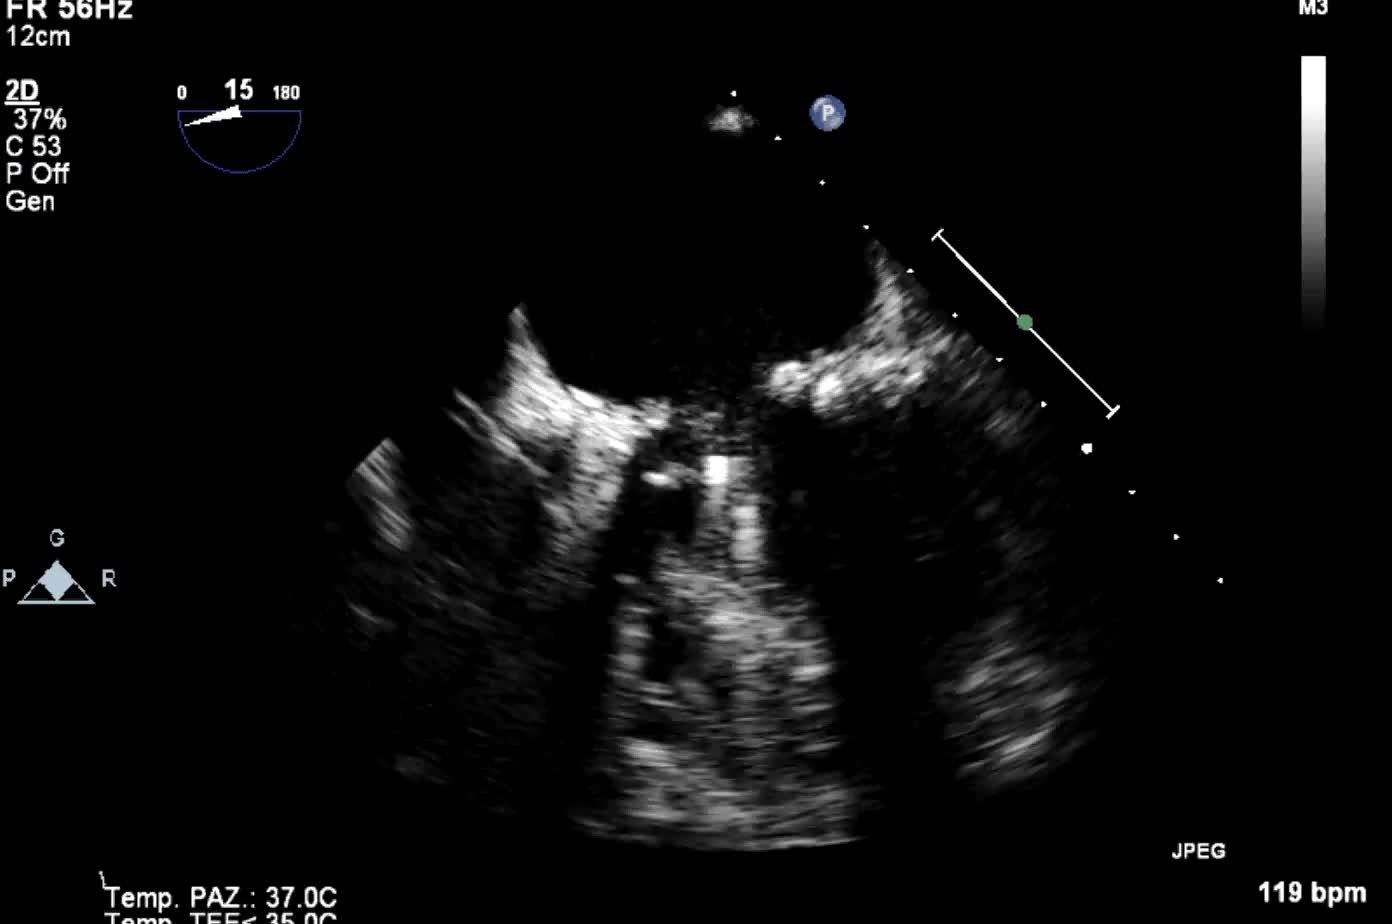

Trombosi protesica

Autore:

Camilla Facchini